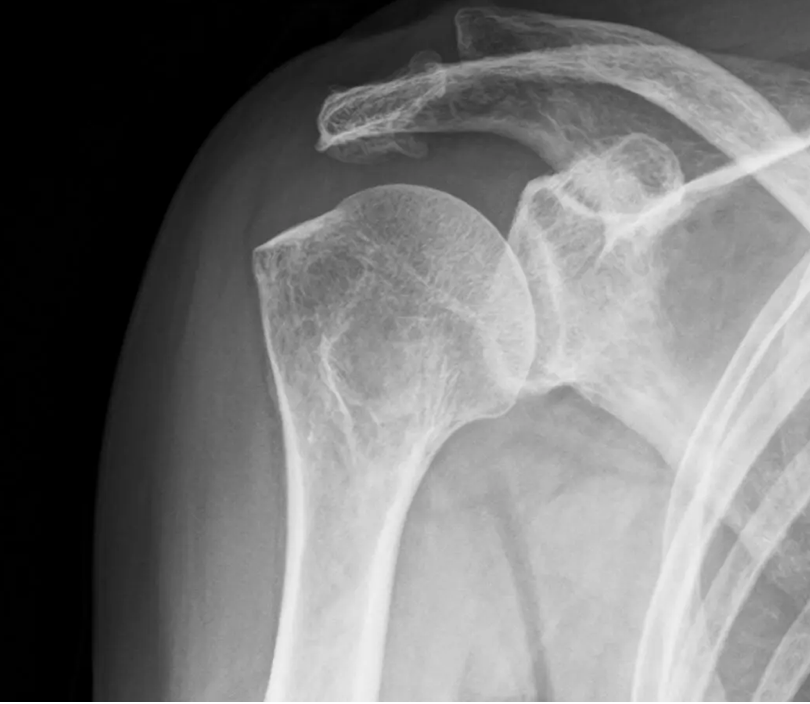

四十肩や五十肩の特徴は、腕を頭上にあげたり後ろに伸ばしたりすると、肩関節に激痛が走ることです。病院に行くと肩関節にステロイド注射をされる場合もありますが、相当腕の良い医師でない限り、鎮痛効果が持続することは期待できません。

なぜなら、この症状の根本原因は、肩関節(正確には肩甲上腕関節)の炎症や腱板の断裂だけではないからです。姿勢のマネジメントを指導して脊柱の湾曲を正常化し、肩甲骨の位置を最適化しない限り根本的な改善には至りません。同時に呼吸の仕方を見直して胸郭の形状を修正することも不可欠です。